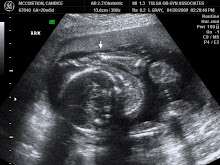

Look by the arrow!!!

Can't miss it!!!